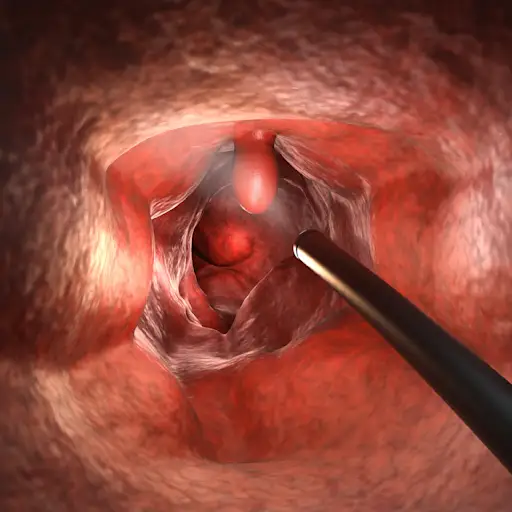

如果您的癌症被归类为阶段肿瘤,这意味着它位于您的结肠上的一个特定点,并没有在您的身体中的任何其他地方传播。科恩博士解释说,在这种情况下,医生通常会在结肠镜检查期间进行简单的息肉去除。如果癌症完全被删除,则此时可能不需要进一步的干预。但是,您的医生将希望密切监视该地区,以确保您在未来几个月甚至几年内保持无癌症。

如果癌症无法通过结肠镜检查完全除去,您的医生可以建议手术切除手术。在此过程中,将与癌细胞的结肠片的片断除去,然后将两个健康的端部一起缝制在一起。“如果我们足够早期捕获癌症并且可以做这种手术,预后通常很好,”哈福塔大学奥古斯塔奥古斯塔奥古斯塔大学格鲁吉亚癌症中心外科肿瘤学局长,博士议长。手术可以打开(通过切入您的胃)或腹腔镜(用微小的切口和管完成)。